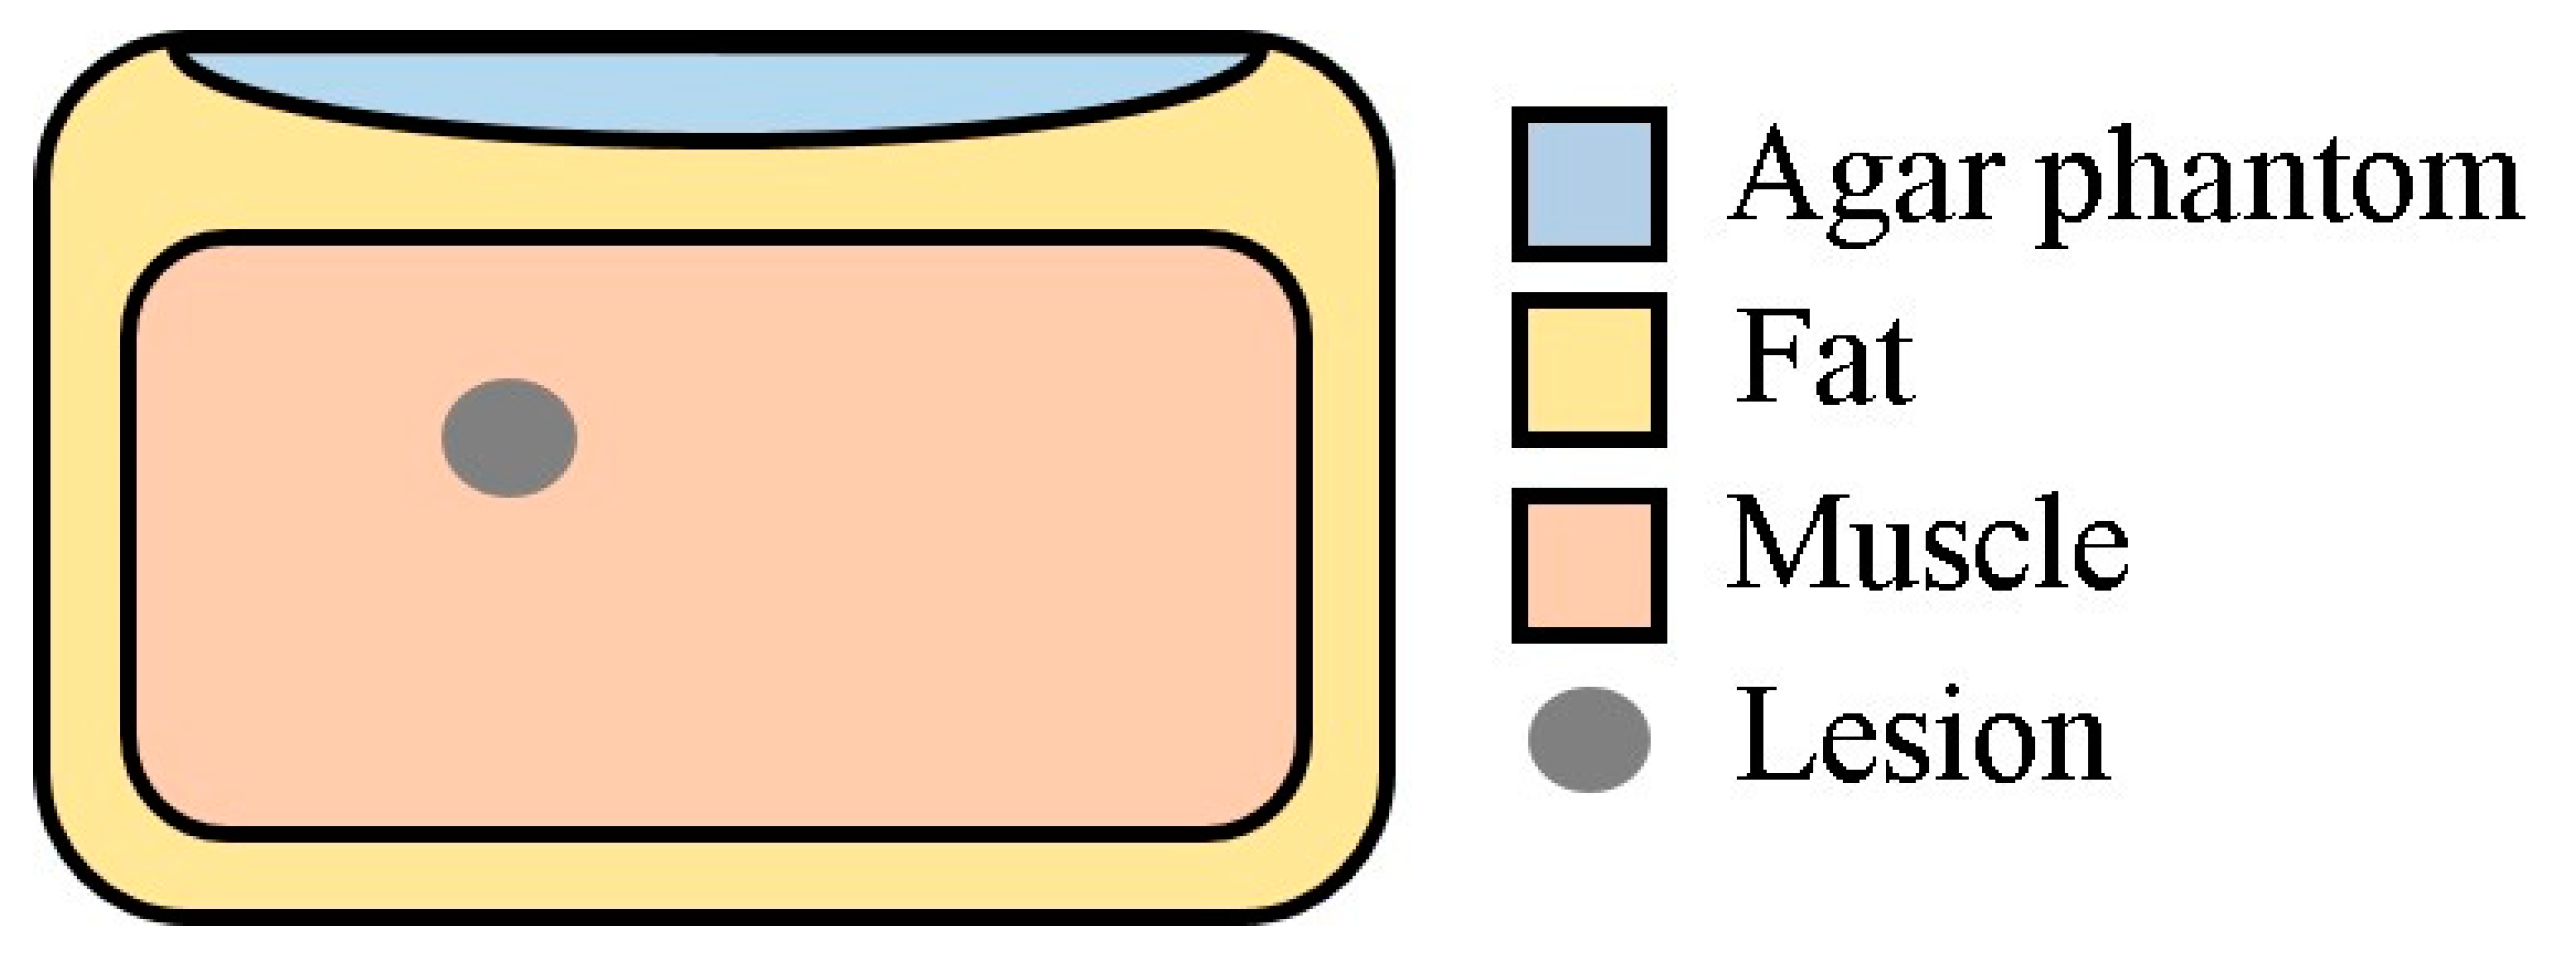

2.4. Experimental Imaging of an Abdominal Phantom using the Proposed Method of Compensating for the Sound Velocity Distribution to Correct Beamforming

3.2. Imaging of an Abdominal Phantom